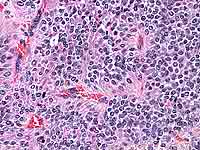

This revealed total occlusion of the right mainstem bronchus with pink-colored

granulation tissue. The tissue was friable and bled easily with the biopsy.

The biopsy was 'typical' for this disease.

DO YOU HAVE AN OPINION OF THE BIOPSY ?